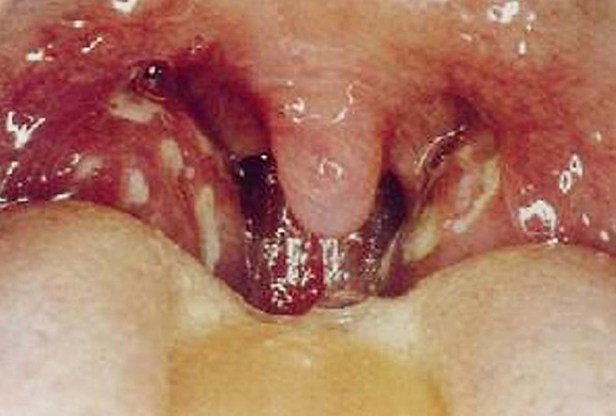

咽部A组乙型溶血性链球菌感染的咽炎、喉炎的儿童(图2-1),在秋、冬、春季患病率高,也是风湿病的高发季节。虽然风湿病的患者血液中发现高效价的抗链球菌抗原的抗体,但在局部(心、血管、关节等处)却无这种细菌感染,炎性病变也非化脓性,说明并不是细菌直接作用所致。

(图2-1)